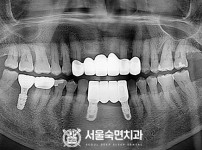

임플란트-전후사진1

임플란트-전후사진2